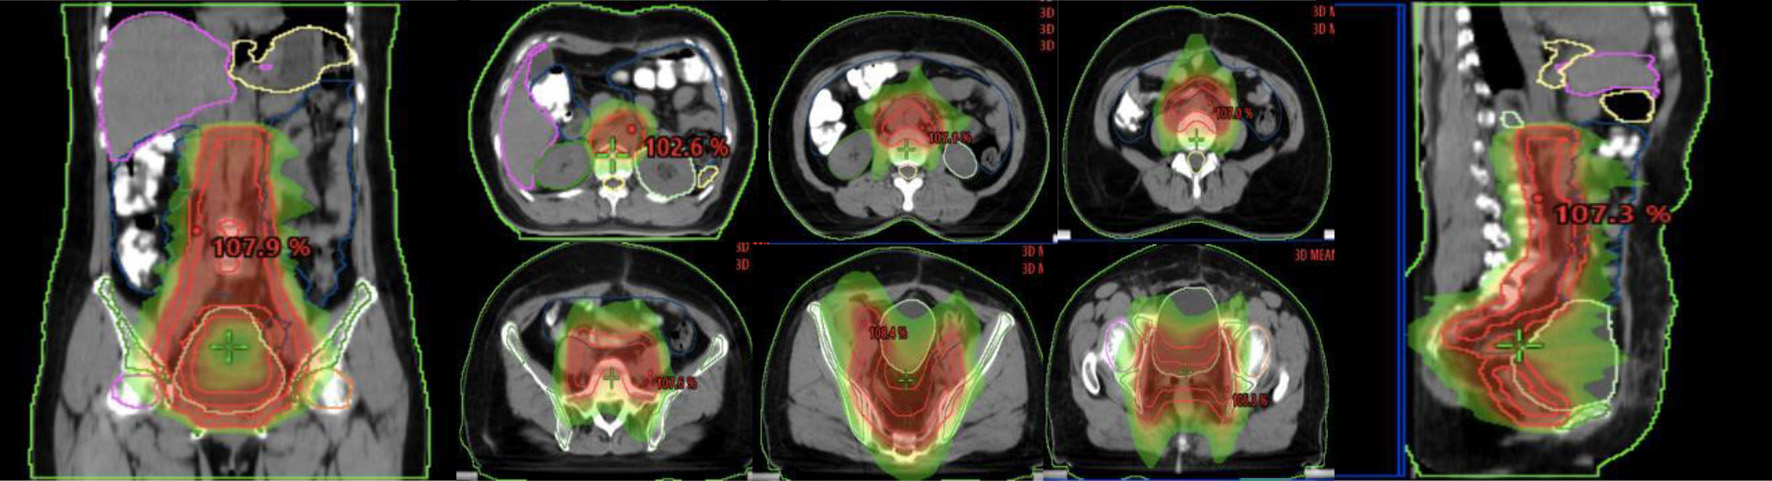

Para-aortic lymphatic drainage area (PALN), vaginal stump and pelvic lymphatic drainage area (common iliac, external iliac, internal iliac, closed foramen region, and anterior sacral region), abdominal aorta PALN (upper border at the level of T12, lower border at the bifurcation of the abdominal aorta): 2 cm external dilatation of left-lateral para-aortic (PALN-LPA), 1 cm external dilatation of the right para-caval (PALN-RPC), and 5 mm external dilatation of aorto-caval (PALN-AC); common iliac lymphatic drainage area (upper border at the bifurcation of the abdominal aorta, lower border at the bifurcation of the common iliac artery): 7 mm external dilatation of the common iliac artery, including bilaterally to the inner edge of the psoas major muscle; internal and external iliac level: 7 mm external dilatation of the internal and external iliac artery, 17 mm anterolateral to the external iliac group. The anterior sacral region: 15 mm anterior to the vertebrae; the closed foramen region: 18 mm of the pelvic wall connecting the internal and external iliac parts. The specific illustration is shown in Figure 1.

![]() Click for large image | Figure 1. Illustration of the abdominopelvic lymphatic drainage area irradiation. |

![]() Click for large image | Figure 3. Failure map for patients treated with APLN. *The yellow line represents the area of APLN (vaginal stump and pelvic lymphatic drainage area (common iliac, external iliac, internal iliac, closed foramen region, and anterior sacral region), abdominal aorta PALN (upper border at the level of T12). The pink line represents the radiation area of WART. The red rods represent LR. The failure map shows 20 patients with LR: 13 para-aortic or pelvic lymph nodes, two vaginal stump, three mesenteric area, and one inguinal and one abdominal wall, and three with recurrence between the area of WART and APLN. APLN: abdominopelvic lymphatic drainage area irradiation; PLAN: para-aortic lymphatic drainage area; WART: whole abdominal radiotherapy; LR: local recurrence. |

Dosimetric validation was collected for normal tissue and target area DVHs, and computer code was written and saved as a Matlab executable program to calculate the EUD for PTV and OAR, which in turn calculated NTCP and TCP. Comparison of planned designs for irradiation of the APLN and WART in five patients showed a significant increase in mean planning target compared to total abdominal irradiation radiotherapy volume (PTV) dose of 10.8 ± 4.4 Gy (25%). Reduced OAR dose was 10.8 ± 4.4 Gy (25%) for liver, 10.8 ± 4.4 Gy (25%) for kidney, 10.8 ± 4.4 Gy (25%) for the small intestine, etc. TCP was increased by 23% (± 21%) and NTCP was reduced by 23% (± 21%) for the liver, kidney, and small intestine. Dosimetric analysis showed that prophylactic irradiation of the abdominopelvic lymphatic drainage area increased the tumor control rate compared with total abdominal irradiation, while ensuring a low dose of abdominopelvic OAR, which validated the clinical efficacy of prophylactic irradiation of the abdominopelvic lymphatic drainage area.

Dosimetric comparison showed that APLN significantly increased the mean PTV dose by 15.08 ± 0.43Gy (50.3%) compared to WART. It significant decreased the OAR dose: 25.37 ± 3.63 Gy for liver, 24.71 ± 3.91 Gy for spleen, 8.77 ± 5.03 Gy for the right kidney, 8.68 ± 5.89 Gy for the left kidney, 8.14 ± 1.51 Gy for small intestine, 24.42 ± 5.72 Gy for stomach, and 3.05 ± 2.00 Gy for spine cord, meanwhile it increased the OAR dose comparing with WART: 6.32 ± 2.61 Gy for the right femoral, 7.26 ± 1.44 Gy for the left femoral, 5.70 ± 4.24 Gy for bladder, 14.04 ± 4.01 Gy for rectum, and 4.93 ± 2.90 Gy for bone marrow. NTCP in the liver, kidney, and small intestine were decreased by 0.04-1.04%.